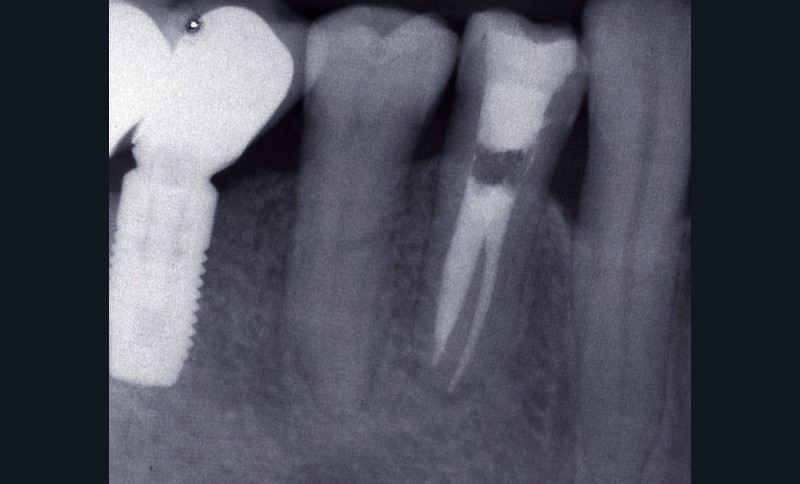

La PAC est fréquemment associée à un silence clinique, expliquant sa découverte généralement fortuite au cours d’une radiographie de contrôle (fig. 2).

Dans certains cas, une douleur à la percussion et éventuellement à la palpation des tissus mous peut être rencontrée. L’image radiographique associée est celle d’une lésion granulomateuse ou d’un kyste. En l’absence de traitement approprié ou d’une diminution des défenses de l’hôte, la lésion peut s’exacerber sous la forme d’un abcès phœnix. La dent devient douloureuse et sensible à la percussion, les tissus mous sont œdematiés et douloureux à la palpation. La présence d’une petite fistule peut parfois être objectivée cliniquement (fig. 3) [13].

La PAC peut perdurer durant de longues années et présenter des phases avec fistulisation durant lesquelles la dent ne présente généralement pas de symptomatologie. Une fermeture spontanée de l’ostium fistulaire entraîne parfois l’exacerbation aiguë sous la forme d’un abcès.